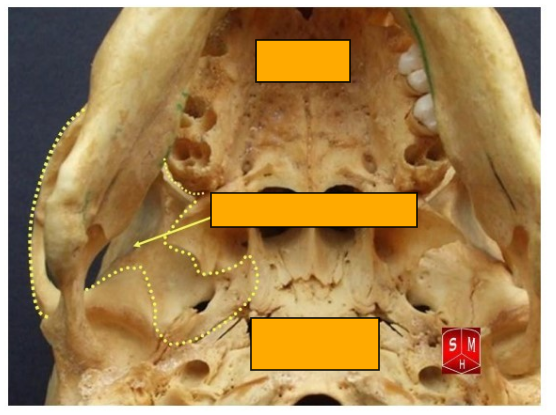

What are the posterior, lateral and anterior attachements of the tentorium cerebelli

posterior- internal occipital protuberance and transverse sulci

lateral- superior border of the petrous part of the temporal bone

anteriorly- anterior and posterior clinoid processes

Anterior, superior and posterior attachements of the falx cerebri

anterior- crista galli

posterior- internal occipital protuberance

superior- internal surface of calvaria along the sagittal suture

Label this image